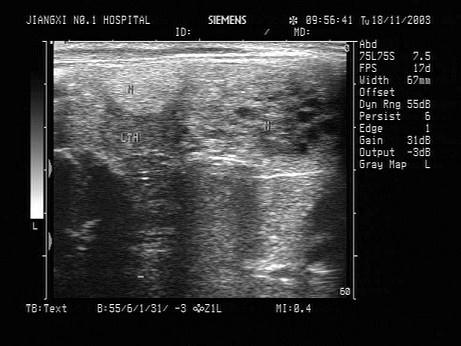

问题 患者,女性,甲状腺肿大。探及多个结节状的强回声光团,其内可见暗区。如图所示,最可能的诊断为?(?)

选项 A.甲状腺功能亢进 B.甲状腺腺瘤 C.甲状腺炎 D.结节性甲状腺肿 E.甲状腺癌

答案 D